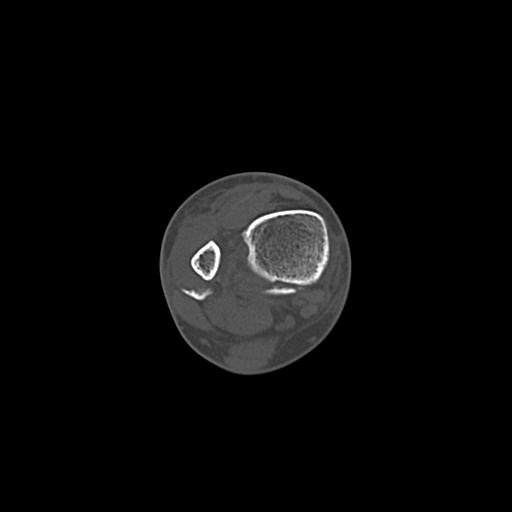

56476 8/28 4R 1/21 2R 左足関節 デジカメ写真 72歳女性 右足関節AS